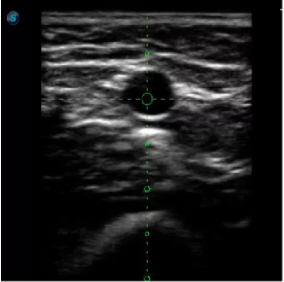

4  置管專用探頭

實時觀察穿刺針進(jìn)入血管的全過程,方便操作及較短的穿刺路徑,智能進(jìn)針尺寸提示,讓置管工作更加輕松,高效。

不同進(jìn)針路徑